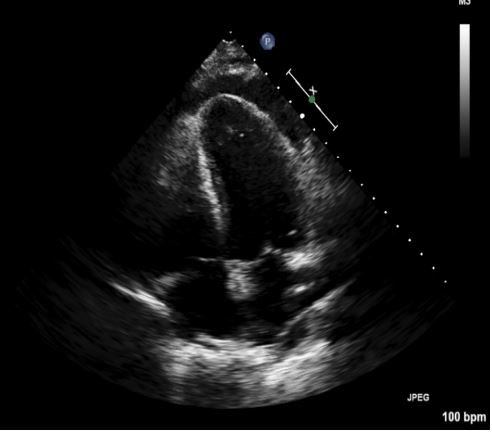

10 days later the patient returned to outpatient cardiology clinic for an echocardiogram and was noted to have a large pericardial effusion along with evidence of impaired relaxation of the left ventricle during diastole (Figure 1). Following transfer to the ED, he was noted to have a heart rate of 113 bpm and blood pressure of 129/70 mmHg; his respiratory rate, oxygen saturation and temperature were within normal limits. A chest x-ray ordered for his mild shortness of breath revealed a massively dilated, air-filled structure in the left upper quadrant with severe compression of the left lung and heart(Figure 2). A CT scan demonstrated massive dilation of a loop of bowel measuring 29 cm x 18 cm x 13 cm centered in the left upper quadrant with possible partial sigmoid volvulus (Figure 3).

Figure 3: Clinical image.